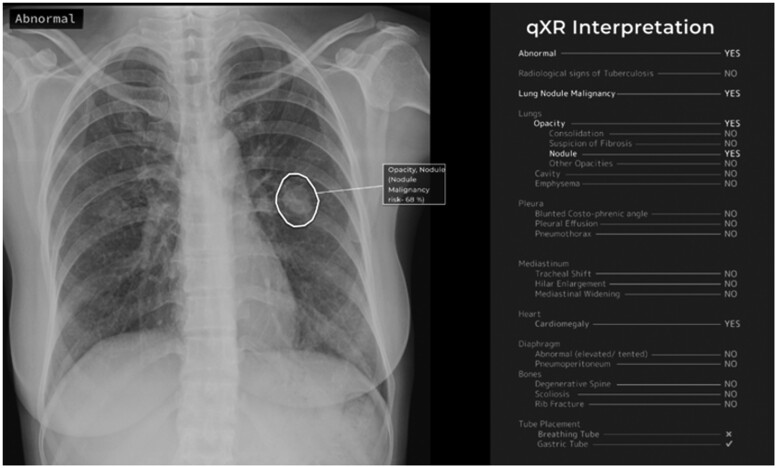

Objective: Artificial intelligence (AI) technology promises to be a powerful tool in addressing the global health challenges posed by tuberculosis (TB). However, evidence for its real-world impact is lacking, which may hinder safe, responsible adoption. This case study addresses this gap by assessing the technical performance, usability and workflow aspects, and health impact of implementing a commercial AI system (qXR by Qure.ai) to support Australian radiologists in diagnosing pulmonary TB.

Materials and methods: A retrospective diagnostic accuracy evaluation was conducted to establish the technical performance of qXR in detecting TB compared to a human radiologist and microbiological reference standard. A qualitative human factors assessment was performed to investigate the user experience and clinical decision-making process of radiologists using qXR. A task productivity analysis was completed to quantify how the radiological screening turnaround time is impacted.

Results: qXR displays near-human performance satisfying the World Health Organization's suggested accuracy profile. Radiologists reported high satisfaction with using qXR based on minimal workflow disruptions, respect for their professional autonomy, and limited increases in workload burden despite poor algorithm explainability. qXR delivers considerable productivity gains for normal cases and optimizes resource allocation through redistributing time from normal to abnormal cases.